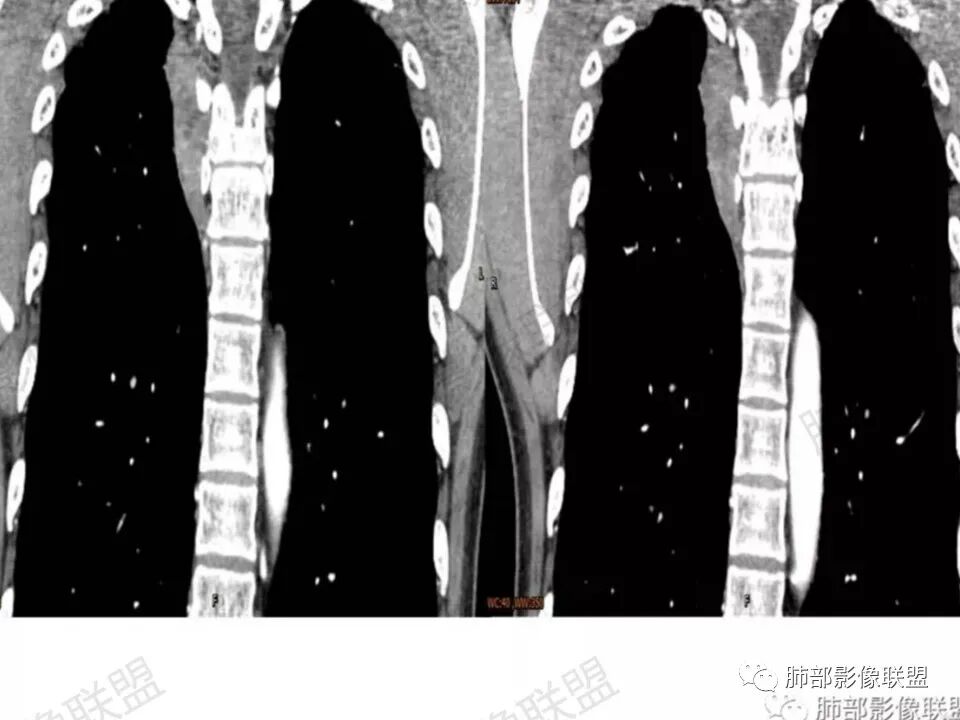

问:这个病例病灶确实邻近椎间孔生长,除了神经源性肿瘤会向椎间孔方向生长,还有什么肿瘤会有这种行为?这个病灶整体形态呈扁平不规则,周围骨质未见破坏,就一定是良性吗?    答:这个病灶明显嵌入式生长,往往提示病灶柔软或有侵袭性,而神经鞘瘤往往有包膜,有张力,典型的形态往往呈类圆形、“逗点形”或“哑铃型”横向延入某一椎间孔内;神经节细胞瘤虽然可以比较柔软,但是具有大量粘液基质,动静脉期强化不明显,延迟强化轻度增强,加之没有钙化,故符合点不多;此外比较柔软的肿瘤如淋巴瘤,但是周围没有肿大淋巴结不太考虑;本例形态不规则的实性肿块,没有明显骨质破坏,倾向具有侵袭性的间叶来源的肿瘤。

问:神经源性肿瘤的生长方式?

答:神经源性肿瘤的解剖位置及形态很重要—沿神经干方向生长走行。后纵膈内神经鞘瘤最常见的是神经根出入椎间孔处,并可沿着肋间神经方向分布,所以后纵膈神经鞘瘤通常横径大,上下径小,这个病例明显上下径长,所以不符合神经鞘瘤;神经节细胞瘤可沿着椎旁上下方向分布(参见上图黄色梭形的神经节),所以表现为上下径长,虽然生长方式符合,但是节细胞瘤以粘液为主,易钙化,该病例成分及强化方式不符合。

病例总结:这个病灶除了发病部位不是很典型,其他影像表现均较符合侵袭性纤维瘤病改变。该病例定位很重要,胸膜来源还是纵膈来源。病灶周围结构虽没有破坏,但是嵌入式生长的实性肿块,符合侵袭性肿块的生物学行为。图像资料完整对诊断尤其重要,CT平扫及各期强化都是相辅相成的,强调MR检查对于侵袭性纤维瘤有鉴别诊断价值。